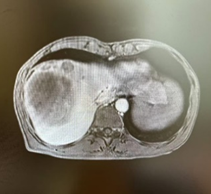

右半肝切除后术中照片 右半肝切除术后2天CT

经术前三维成像评估右半肝切除后残肝体积为标准肝体积的50%,但吲哚箐绿(ICG)15分钟滞留率(ICG-R15)达25%,暂停手术,于是加强营养支持治疗,一周后复查ICG15分钟滞留率为14%,最后经肝胆胰外科专家组讨论不符合腹腔镜肝切除要求,决定行前入路右半肝切除术。右上腹斜切口进腹,探查见肝脏呈轻度肝硬化,两个肿瘤直径接近10.0cm的巨大肿瘤占据半肝,一个于包膜外可见,一个位于肝实质内,周围数个微小结节,未见肝内转移灶和腹腔转移灶,为避免术中不适当挤压引起肿瘤经血管转移和肿瘤破裂,先切断肝圆韧带和肝镰状韧带,解剖第二肝门,显露肝右和肝中静脉窝,然后切除胆囊,解剖第一肝门,鞘外分离右肝蒂,预阻断后见右肝缺血明显,除一个微小结节略偏向S4段外,肿瘤全部位于右肝缺血线内,于缺血性和S4段结节稍左侧约1.0cm画切肝线,术中超声证实肝中静脉位于切线下方、全部肿瘤位于切线右侧,结扎右肝蒂,以15+5min模式间歇性阻断肝门,原位离断左右肝之间肝实质,结扎切断肝断面血管和胆管,到达右肝蒂时确认右肝蒂后右切割闭合器离断右肝蒂,继续沿中肝静脉右侧离断肝实质,直至下腔静脉前壁,至此完全离断左右半肝之间的肝实质,然后于第三肝门显露、结扎、离断右侧肝短静脉,最后显露右肝静脉,切割闭合器离断右肝静脉,于Laennec膜外钝性分离肝裸区,离断右三角韧带和右冠状韧带,至此已原位肝切除术切除包括所有肝肿瘤的右半肝,移除切除物。肝癌切除术后余肝血运及回流良好,肝断面彻底止血后置橡胶引流管,关闭切口,术毕。